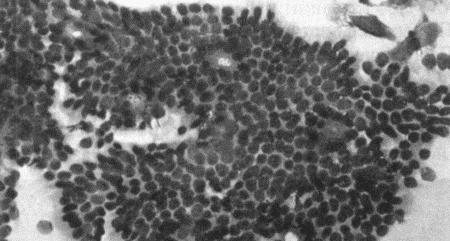

Вагинальная цитология

Повышение концентрации эстрадиола в период проэструса стимулирует деление клеток в базальных слоях вагинального эпителия, но затем концентрация эстрадиола, а соответственно и эндокринная поддержка образования нового, многослойного эпителия снижается, поэтому в образце обнаруживается больше мертвых ороговевших клеток. По мере развития проэструса снижается количество эпителиальных клеток, содержащих ядро. С начала до середины проэструса в вагинальных мазках обнаруживают повышенное содержание эритроцитов. Пик ороговения совпадает с началом повышения концентрации прогестерона; однако в начале эструса исследование не обнаруживает характерных особенностей, которые могли бы указывать на начало фертильного периода. Как правило, такой период наступает несколькими днями позже (табл. 1.1). Тем не менее вагинальная цитология остается популярным методом определения репродуктивного статуса суки из-за своей дешевизны, простоты и доступности. Для получения образца используют ватный тампон, предпочтительно небольшой, который вводят во влагалище и осторожно берут мазок. Полученные клетки помещают под микроскоп, а затем окрашивают контрастным (трихромом) или неконтрастным (например, препаратом Diff-Quik) веществом. При таком окрашивании мертвые кератинизированные клетки становятся оранжевыми, тогда как активные ядерные клетки, а также базальные и парабазальные эпителиальные клетки приобретают различные оттенки от голубого до зеленого.

Ближе к окончанию эструса вагинальные выделения претерпевают характерные изменения (снова выявляются эпителиальные клетки, содержащие ядро, и появляется большое количество лейкоцитов). Такая картина обычно наблюдается через 7–9 дней после пика ЛГ и известна как «вагинальный мазок метэструса». Изменению характера выделений предшествует переходный период, характеризующийся возрастающим количеством активных клеток и указывающий на окончание фертильного периода и эструса (табл. 1.1).

Вагинальная цитология весьма информативна в плане определения фазы эстрального цикла, однако значительные расхождения во времени появления основных признаков эструса по отношению к пику фертильности ограничивает применение указанной методики.

Фиг. 2.2.

Вагинальные выделения кошки (а). Выделения, типичные для фазы эструса. Большая часть клеток представляет собой безъядерные кератинизированные клетки или клетки с пикнотическим ядром. Присутствуют промежуточные клетки (b). Выделения, характерные для метэструса, — «течки», иногда наблюдаемой у кошек в конце эструса. Присутствуют поверхностные и промежуточные клетки, повышено содержание лейкоцитов. Этот короткий метэструс наблюдается в течение 24–48 часов (см. Приложение)